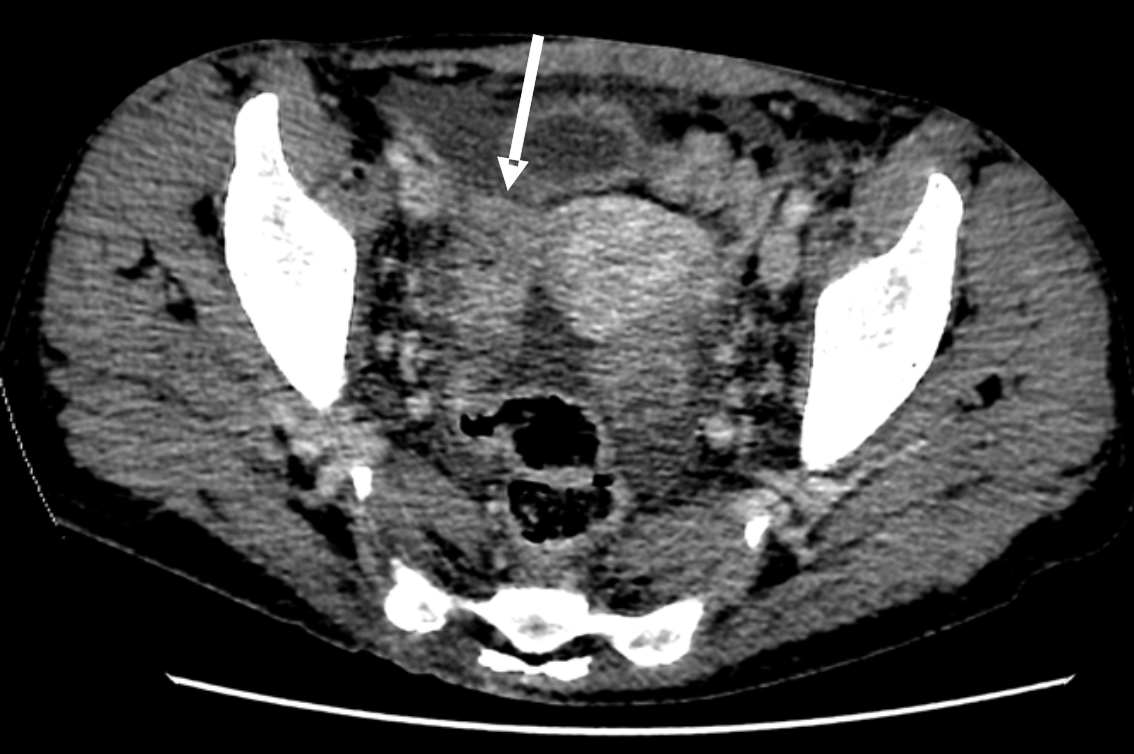

По данным компьютерной томографии (КТ) органов грудной клетки выявлены увеличенные до 16 мм лимфатические узлы метастатического характера. На КТ органов брюшной полости обнаружены образования по малой кривизне желудка (стенка неравномерно утолщена) и множественные вторично измененные лимфоузлы (парагастрально, в забрюшинном пространстве и брюшной полости), а также образование левого надпочечника до 36 мм по короткой оси (рис. 1), вторичного характера, в малом тазу определяется жидкость, метастаз в яичники (рис. 2), асцит, лимфаденопатия, жировой гепатоз. При выполнении магнитно-резонансной томографии (МРТ) выявлена картина единичных очагов сосудистого генеза белого вещества больших полушарий головного мозга, структурная неоднородность гипофиза в левых отделах.

Рис. 2. КТ органов полости малого таза. Опухоль Крукенберга справа (указан стрелкой)